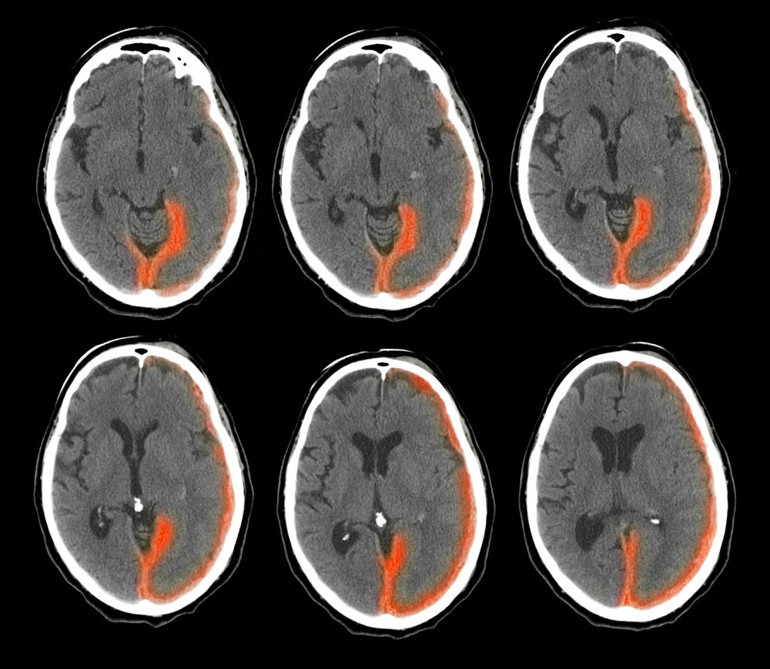

Bilgisayarlı Tomografi taramasında beyin kanaması tespit edilince acilen helikopterle Brisbane'deki yoğun bakım ünitesine kaldırıldı.

Prosedürlerden biri, beyinde oluşan basıncı azaltmak için bir beyin omurilik sıvısı drenajının yerleştirilmesini içeriyordu. Ancak beyin sapındaki kanama ameliyat için çok genişti.

Kaynak: Daily Mailİnme, beyne giden kan akışının kesilmesi ve beyin hücrelerinin ölmesiyle meydana gelir. Hasar uzun süreli sakatlığa yol açabilir ve insanların düşünme ve hissetme biçimlerini etkileyebilir.En yaygın neden, iskemik inme olarak bilinen beyni besleyen arterleri tıkayan yağ birikintileri veya kan pıhtısıdır. Bu, kan damarlarının zamanla plaklar tarafından daraltıldığı veya tıkandığı kardiyovasküler hastalık nedeniyle olur. Bunlar, ateroskleroz olarak bilinen bir süreçte arter duvarlarında biriken kolesterol, kalsiyum ve diğer maddelerden oluşur.

Hemorajik inme olarak adlandırılan diğer atak türü ise beyinde bir kan damarı hasar aldığında ve kanı organa sızdırmaya başladığında meydana gelir.